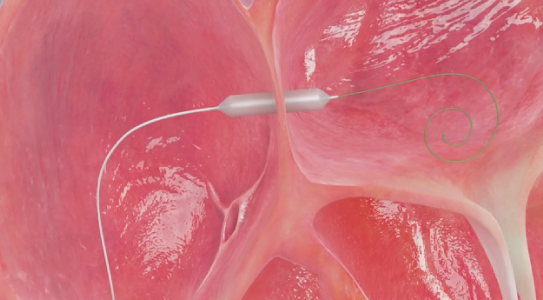

为攻克精准控制分流量的技术难题,荆志成教授带领团队采用“医工交叉”的创新研究策略。在对前期研究数据进行大量分析计算的基础上,制定了设定造口术后目标动脉血氧饱和度,计算目标分流量,再使用导管测定血流动力学参数和血氧含量数据,计算目标分流口径的策略,解决了如何精确计算患者所需要的房间隔造口的直径这一关键问题。随后,荆志成教授团队与武汉唯柯医疗科技有限公司紧密合作,设计了新型心房分流器实现精准控制分流量。同时设计了多种分流器孔径型号,且分流器设置偏心横向螺母端头,释放后可回收、可更换、可二次干预,只为用精心的设计确保经皮房间隔造口术为每一位患者带来最大获益。